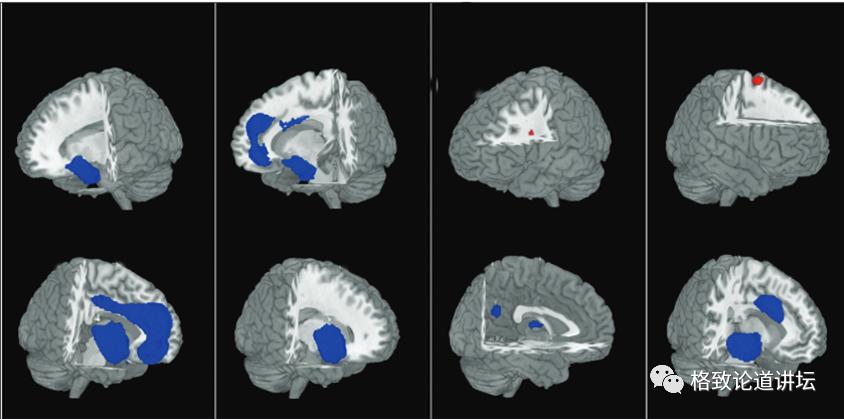

从功能核磁共振的结果可以看出,大脑的蓝色区域是有功能下降和体积缩小的,这些区域是管我们的情绪、认知、注意力、执行功能的,而红色部分跟功能调节、执行、操作有关。

从这些图可以看出,双相是由大脑病理生理改变导致的,而药物有逆转病理改变的功能,药物不仅会使神经细胞修复,而且能使神经的各个区域,尤其像额叶皮质海马这些区域的体积增大,起到修复神经的作用